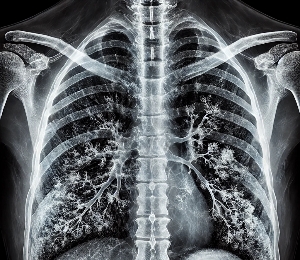

폐렴 회복에 효과적인 음식과 폐 건강을 위한 영양 가이드

폐렴은 폐 조직에 염증이 생겨 호흡이 어려워지고, 심한 경우 폐 기능 저하로 이어질 수 있는 심각한 질환입니다.

병원에서의 엑스레이검사 및 정환한 약물치료를 한후에 완치후 체력 회복차 참고 하시기 바라며